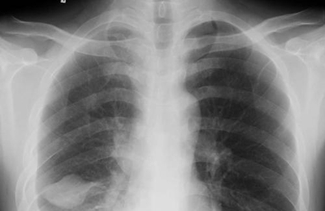

天然對(duì)比:該概念起源于傳統(tǒng)放射學(xué)。指X線照片上,人體組織的模擬影像固有的、肉眼可分辨的光學(xué)密度差別。

影像對(duì)比度:包括兩層含義,一是指照片顯示的模擬影像上相鄰兩點(diǎn)間的光學(xué)密度的差別,即照片對(duì)比度;二是俠義的影像對(duì)比度,系指去處光學(xué)對(duì)比因素,僅反映物體成分的對(duì)比度。在傳統(tǒng)放射診斷學(xué)領(lǐng)域相當(dāng)于X線對(duì)比度。